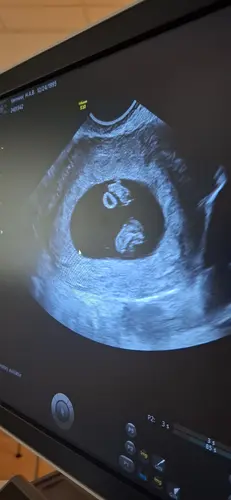

Dit was onze echo. Die cirkel is de dooierzak.Ik ben heel benieuwd hoe de volgende echo eruit ziet